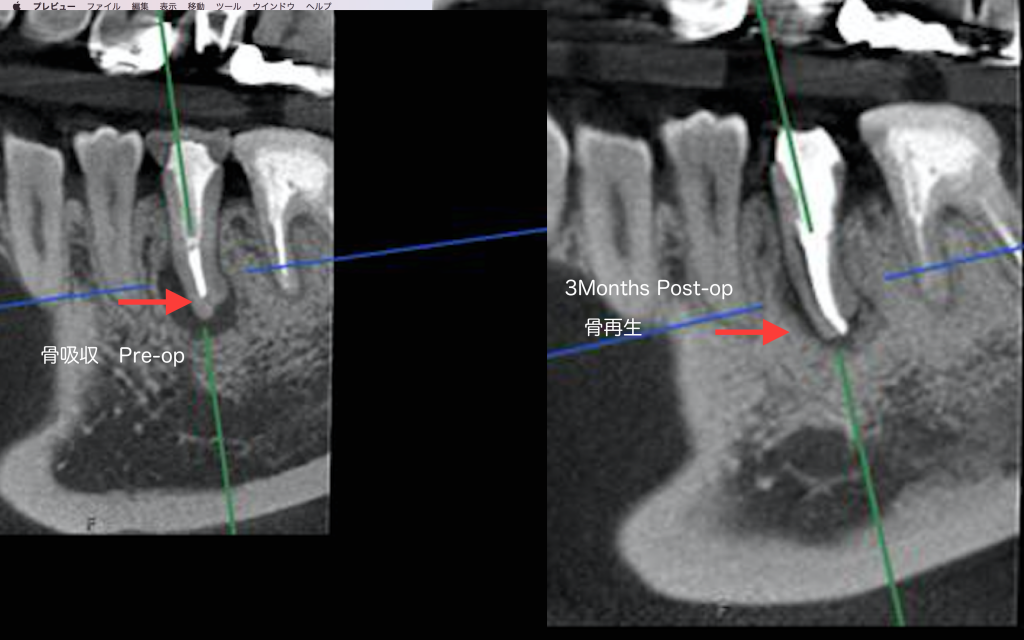

こちらの患者様は前医から歯が割れているかも知れないと抜歯を勧められましたが、根管治療により3ヶ月後治癒傾向を認めました。

正しく行われる根管治療の威力は素晴らしい。

しかしながらこのような結果になるのは、マイクロスコープ・CTなどの器械設備、術者の技量と長時間の治療時間が必要です。

今後は益々膿の部分が小さくなり、骨が再生すると思います。